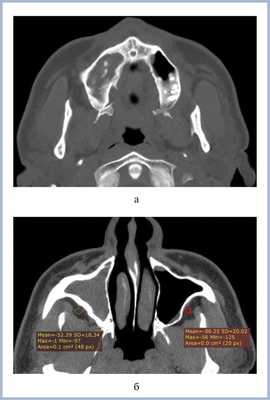

Воспалительные изменения слизистой оболочки верхнечелюстной пазухи, существующие в течение длительного времени, вовлекают в процесс костную стенку. На компьютерных томограммах отмечается утолщение костной стенки в костном режиме и появление «оптического эффекта» — уплотнение стенки в 1,5—3 раза за счет отека надкостницы — при просмотре в мягкотканом режиме (рис. 1, а, б) [9]. При одностороннем процессе, характерном для одонтогенного поражения, на контралатеральной интактной стороне такого эффекта не определяется.

Рис. 1. Рентгеновская компьютерная томограмма околоносовых пазух. Коронарная проекция: мягкотканное окно (а) и костное окно (б).